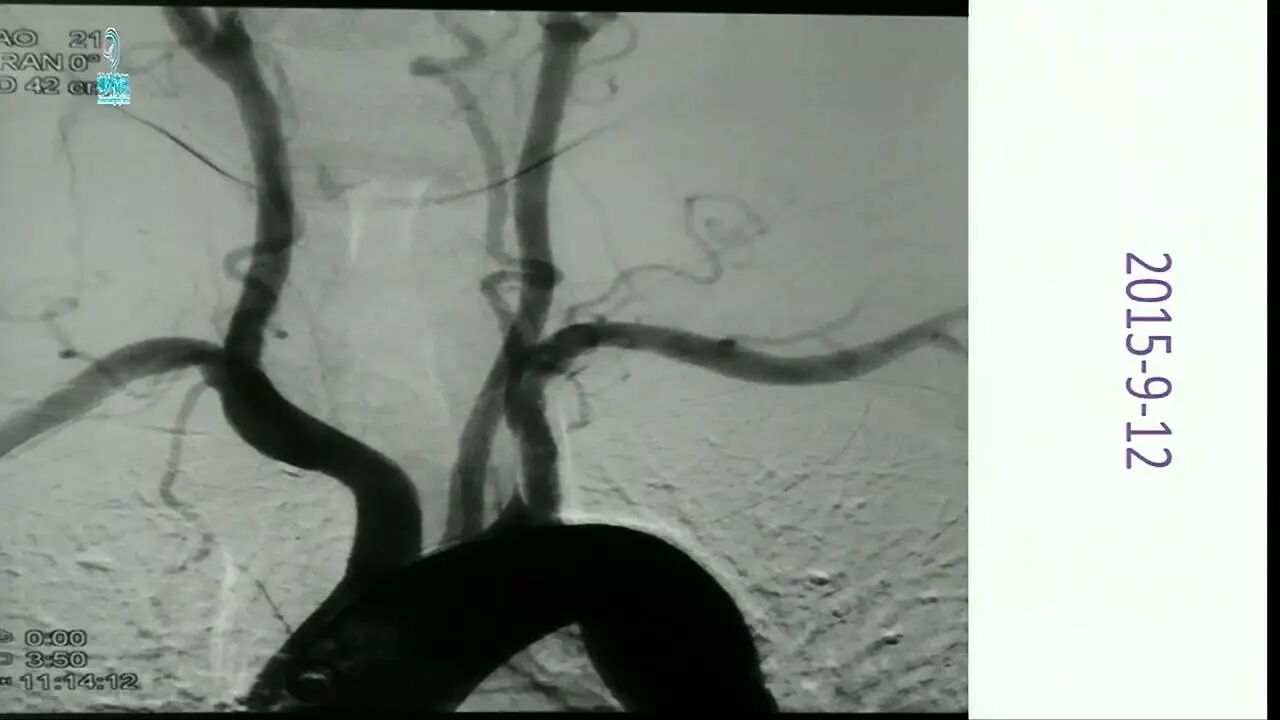

Enterprise支架在缺血性脑血管病中的应用